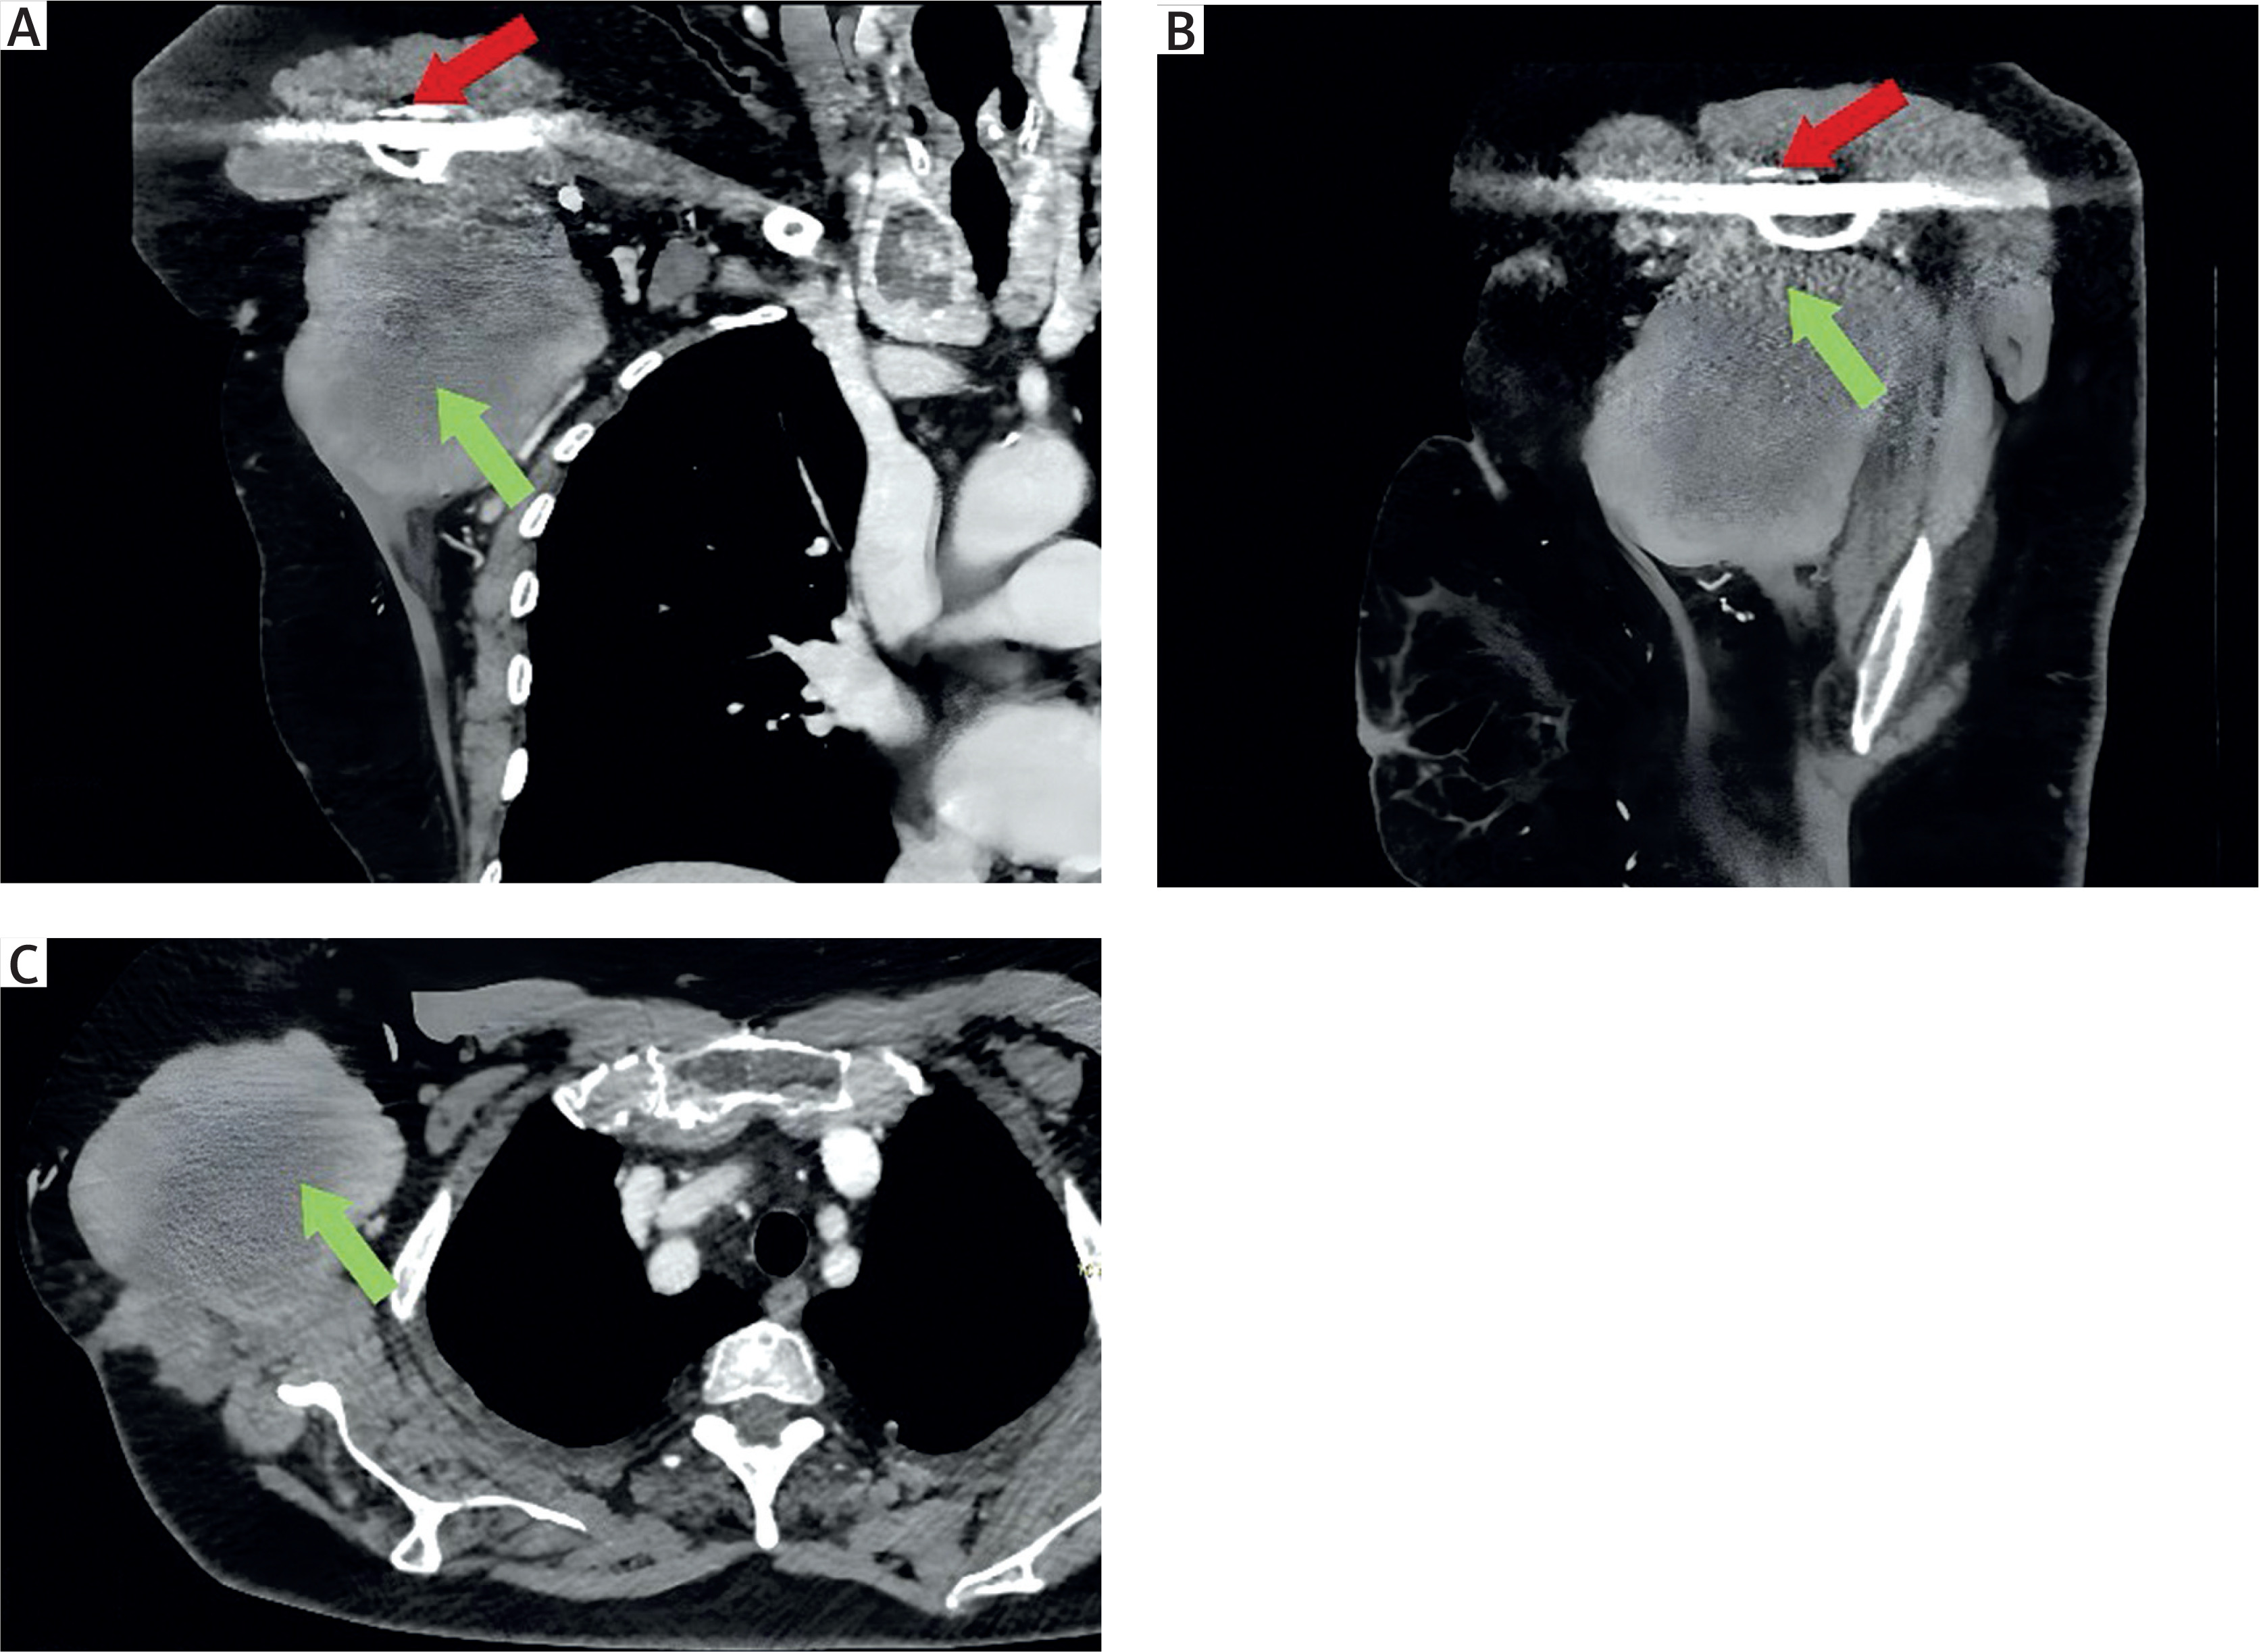

A surgical biopsy was performed, demonstrating a fibrotic lesion. Based on the imaging and histological results, surgical excision was indicated. The lesion fully occupied the axillary cavity and was firmly adherent in part to several fibers of the latissimus dorsi muscle, which were consequently sacrificed, while no vascular or nervous infiltration was detected, although the lesion presented strong adhesion to vascular and nervous structures (axillary vein and artery, brachial plexus fibers). Additionally, the lesion was closely adherent to the titanium plate of the previous orthopedic intervention, suggesting a possible origin from this event. Finally, after blunt and scalpel dissection, the lesion was completely removed with macroscopic free margins (Figure 2). The final histological examination confirmed fibromatous tumor, with a typical immunohistochemical profile: SMA (+), Caldesmon (–), cytokeratin AE1-AE2 (–), S100 (–) and low Ki-67 (3–5%).

Figure 2

Intraoperative image of a thoracic wall mass. A – Visualization of progressive dissection of the tumor from adjacent tissues during the excision phase. B – Postoperative image of the surgically resected lesion